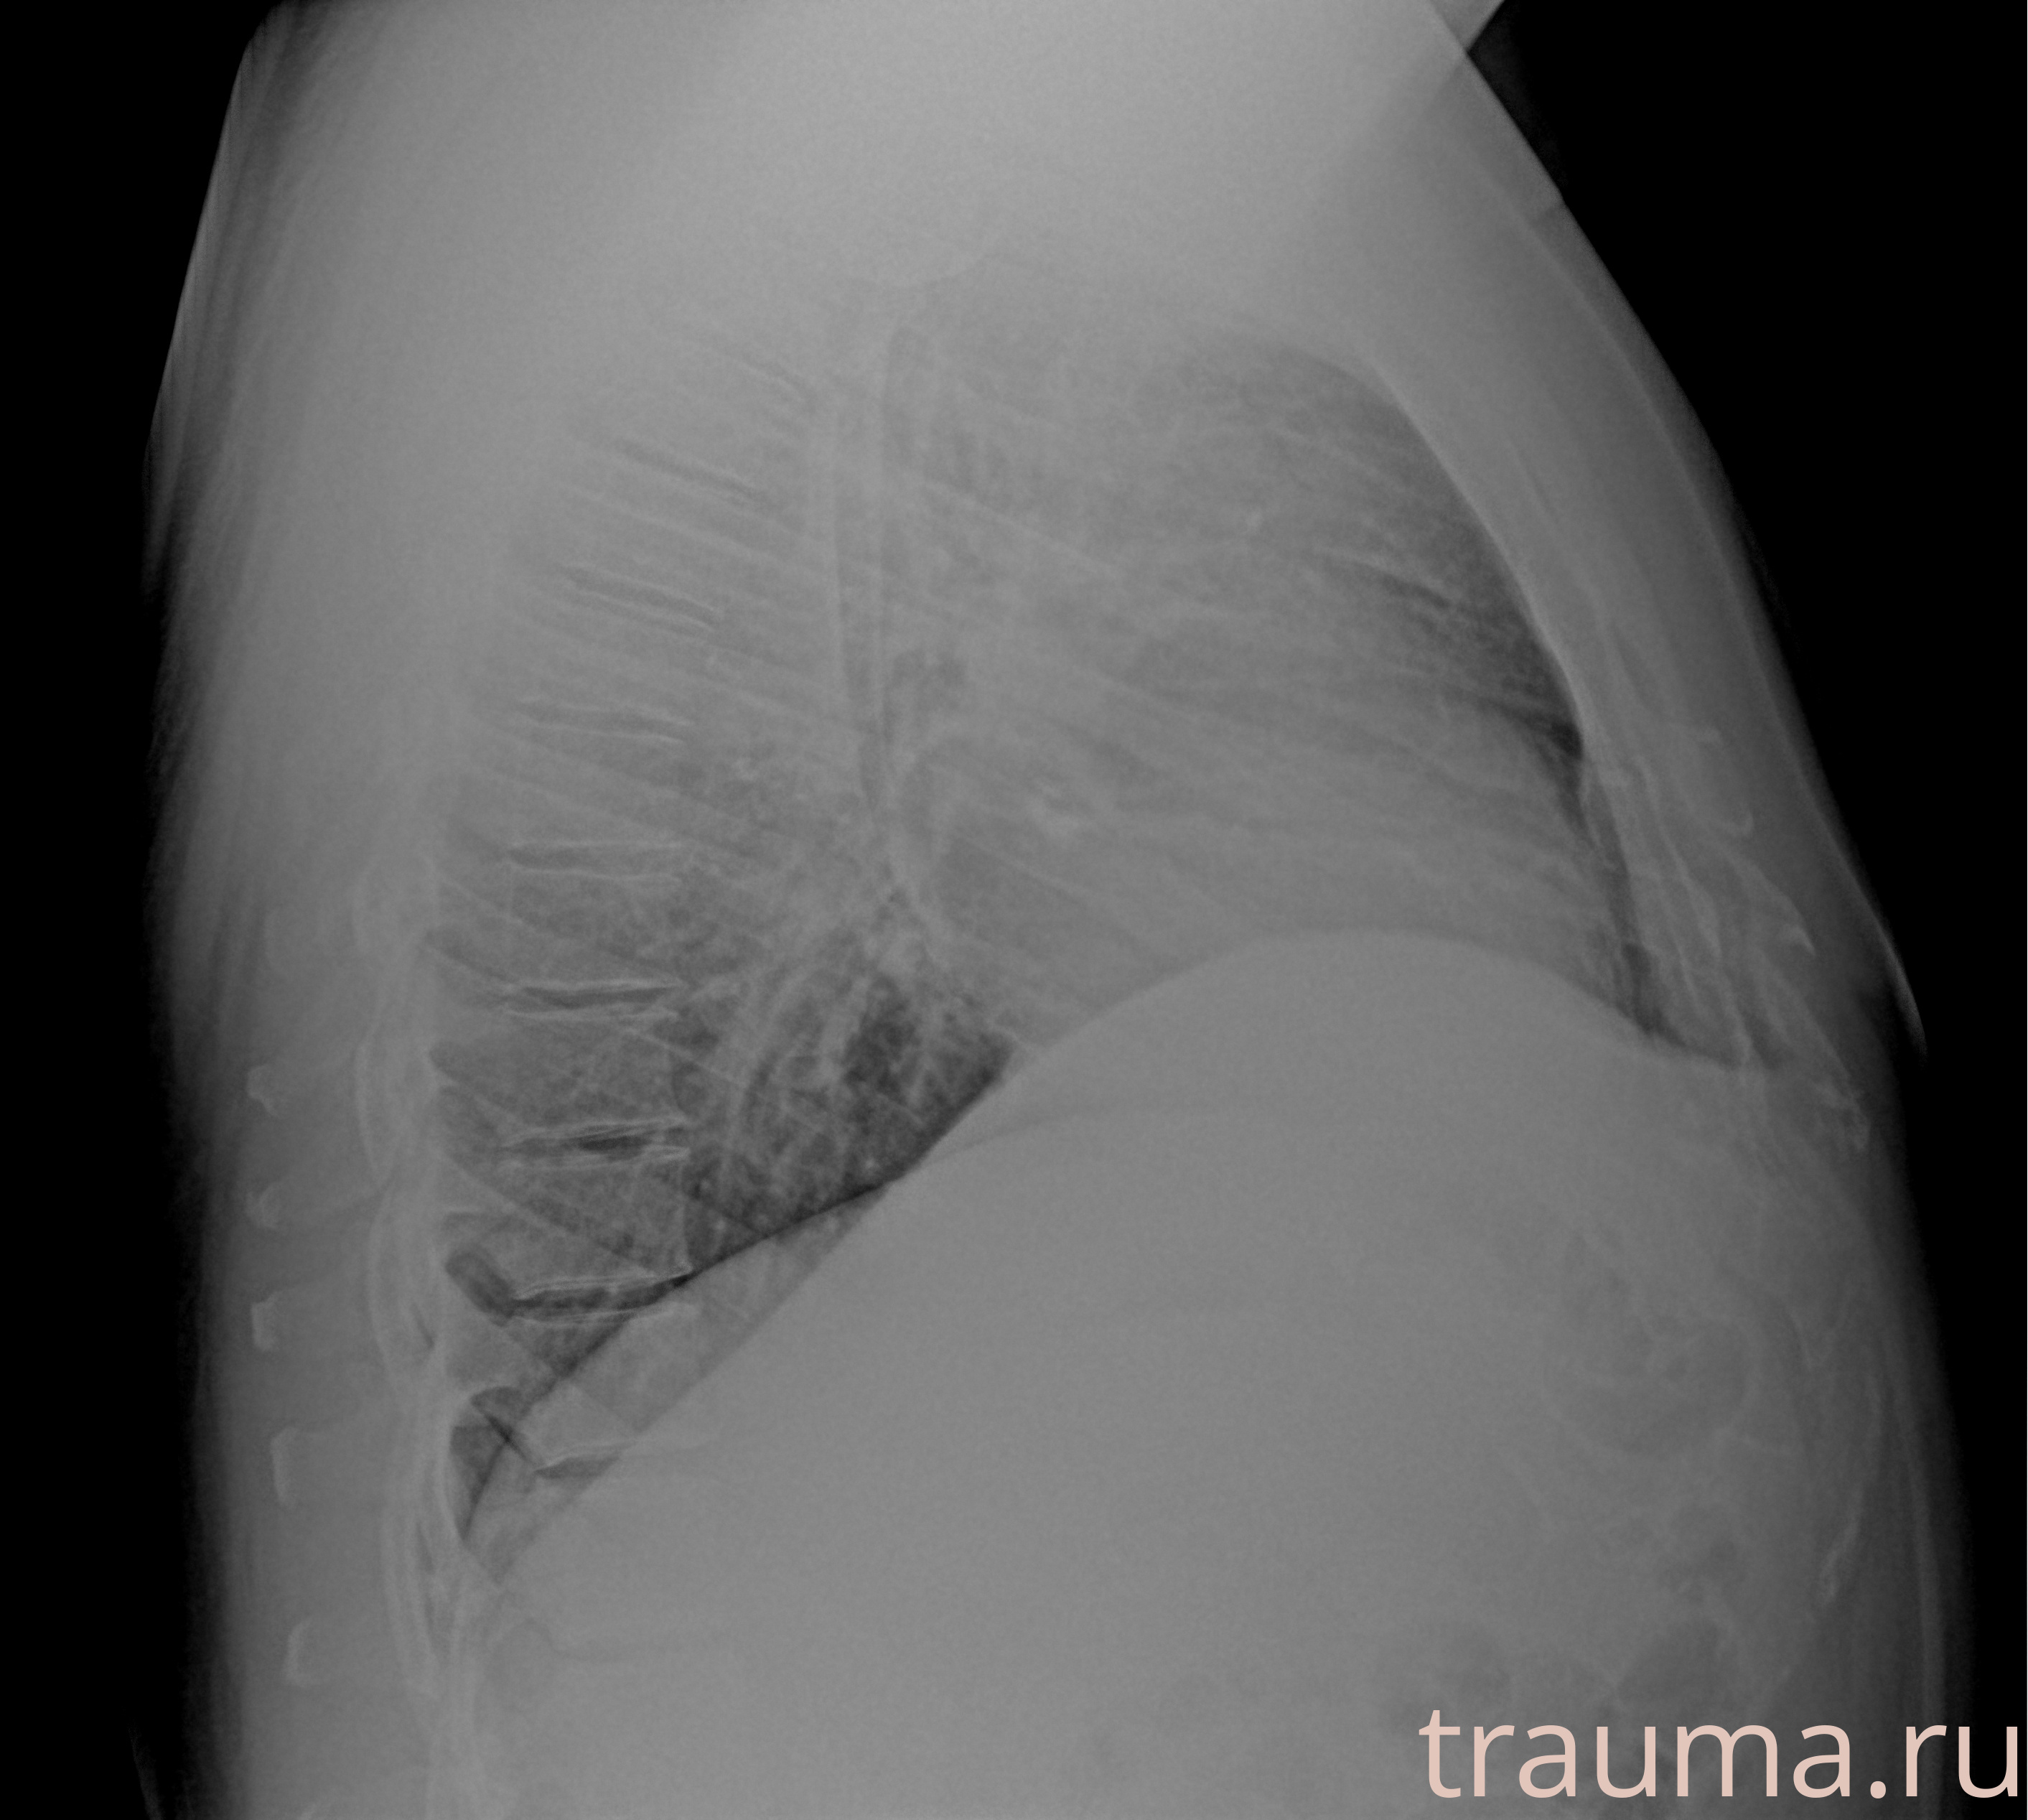

Рентгенограммы

Рентген на дому: по вашему адресу приезжает врач-рентгенолог, травматолог-ортопед с мобильным рентгеновским аппаратом, проводит диагностику травмы или заболевания, делает необходимые рентгенограммы, дает рекомендации по дальнейшему лечению. Получить качественные снимки в домашних условиях возможно благодаря уникальной методике, разработанной МосРентген Центром для института  Склифосовского